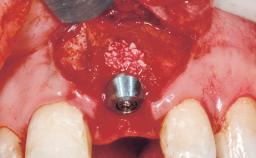

Immediate Placement of an Implant in a Maxillary Right Central Incisor Site

A 30-year-old female patient was referred to the office for the treatment of tooth 11. Her chief concern at the initial visit was to inquire, “Why is my tooth pink?” Upon clinical examination, it was determined that tooth 11 had a previous history of trauma and that the clinical crown had become noticeably pink in color as a result of internal resorption. This diagnosis was confirmed radiographically, indicating a large radiolucency involving the central and distal portions of the clinical crown. It was determined that restoration of this tooth was not possible, and that extraction was indicated. The presence of a mid-line diastema, which the patient wanted to reproduce, directed the treatment plan for tooth replacement utilizing a dental implant.